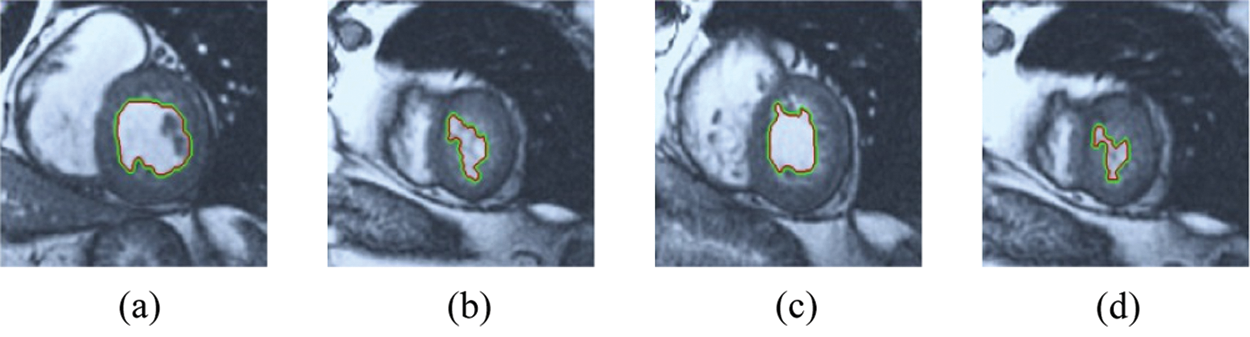

The BRW, HSRW, and ERW medical imaging segmentation schemes are executed on MATLAB, and examined on a short-axis of 3D multi-slices CMRI dataset [27]. Several segmentation performance metrics are utilized such as Dice Metric (DM), the Haussdorff distance (HS), and the Peak signal to noise ratio (PSNR). The BRW, HSRW, and ERW segmentation schemes are executed on a short-axis of 3D multi-slices CMRI datasets. The same multilayer CMRI dataset is segmented using various random walk methods. The presented results were obtained through using BRW, HSRW and ERW methods on five different groups of patients; each group contains 25 subject of multilayer CMR dataset. Experimental results illustrate that the BRW method can achieve a good segmentation of the LV cavity. The results of the HSRW algorithm have very comparable similarities to BRW, but with a slightly less efficiency and a much higher execution rate. Pre-calculations reduce the performance online time in offline mode. The average time of HSRW equals to 0.09 seconds for each slide. Raising the rate of K will improve the comparison and makes the process of segmentation more precise, but also reduces the execution time. The ERW technique results illustrate that this method has the greatest efficiency of segmentation. Figs. 5 to 7 show the resulting images of the BRW segmentation method on five sets of sample data. HSRW with pre-calculation segmentation method is applied on the same sets of sample data and illustrated in Figs. 8 to 10. Figs. 11–13 show the high efficiency segmentation using the ERW method with an earlier model for the same sets of sample data. The results of the Random Walk segmentation overcame the potential restrictions of the prior art CMR methods. The performance of segmentation is fast compared to segmentation methods based on edge and region. BRW precedes into account the properties of regions and edges, as shown in Figs. 5–7. Looking at the image as a graph, the technique makes it possible to integrate pixel relations with neighboring pixels. As a result, segmentation produces good quality BRW technique sections when their qualitative accuracy is compared to the ground truth, and this is also evident from the Tab. 1 measurements in the diastolic and systolic phases in Tab. 2 as well as in the complete cardiac cycle noticed. Figs. 8–10 illustrate the HSRW results. There are no dissimilarities observed in furthermost cases of CMR slides in the figures, but the correspondence measurements of the DM, PSNR and HS coefficients present that the results of the HSRW technique are worse than those of the BRW method. This presents that HSRW is an effective estimation of the random walk influence as mentioned in Tab. 1 and throughout the cardiac cycle in Tab. 2. The values of PSNR and DM are lower, whereas HS is higher than the BRW method, but with slight dissimilarities between HSRW and BRW methods throughout the blood circulation. The impact of execution eigenvectors pre-calculations is perfect when the execution time is faster than the BRW method and, in fact, more efficient than other segmentation method for LV heart segmentation. With the identical dataset, the ERW method shows a significant enhancement in efficiency, as presented in Figs. 11–13. From the scores, we can see that the segmentation is smoother and cleaner. The ERW method considers boundaries and areas, such as BRW, using the relations between adjacent pixels in the image. It also considers the additional regional advantage by including the assumptions that affect the results of the segmentation. Mean segmentation quality measurements are computed from the segmented images using correspondence measurements for instance DM, HS, and PSNR and verified for each method in the diastolic and systolic stages as presented in Tab. 1. Based on results, it can be determined that methods of random walk are enhanced in diastolic diagnosis and that their outcomes in the systolic stage are also of good efficiency. The results of the random walk segmentation methods in the complete blood circulation are shown in Tab. 2. The cardiac cycle similarity amounts indicate that DM and PSNR capacities of ERW are improved than the corresponding capacities in the case of the HSRW and BRW approaches; however, the HS measurements are lower than the equivalent measurements, as illustrated in Tab. 2. This designates that the ERW technique is the furthermost accurate segmentation technique among all the approaches stated above. The ERW technique has the uppermost value of PSNR, and the HSRW method has the lowermost value that denotes the uppermost speed in segmentation process.

Figure 11: ERW results for the first samples set

Figure 12: ERW results for the second samples set

Figure 13: ERW results for the third samples set